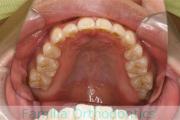

No.22V-264

- 主な症状:

- 上顎前突

- 年齢:

- 23歳

- 性別:

- 女性

- 主な使用装置:

- Invisalign

- 治療にかかった費用:

- 90万円

出っ歯と下の歯のガタガタを治したいということで来院されました。下顎の後退はありましたが、小臼歯非抜歯で上顎の歯列を遠心に移動し、それからインビザラインにて排列を行いました。2年強、30回程度の通院が必要でした。インビザライン/Invisalign®(薬機法および医薬品副作用被害救済制度の対象外)には、患者さんの使用時間が治療の成否を左右するリスクがあります。

- ≫治療前

-

上顎

下顎

前歯の関係など

右側

正面

左側

- ≫治療後